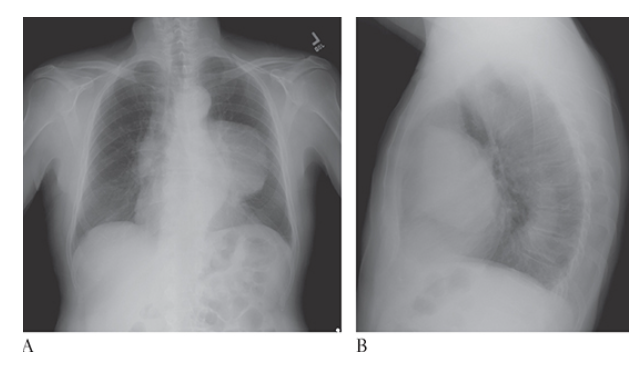

What is A

Thymoma. Posteroanterior (PA) and lateral

What is B

Thymoma. Posteroanterior (PA) chest radiographs show a large left anterior mediastinal mass projecting over the left lung.